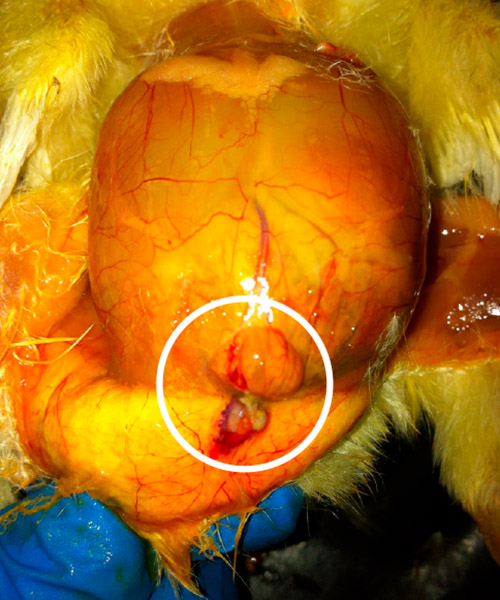

Betent navle og omliggende vev.